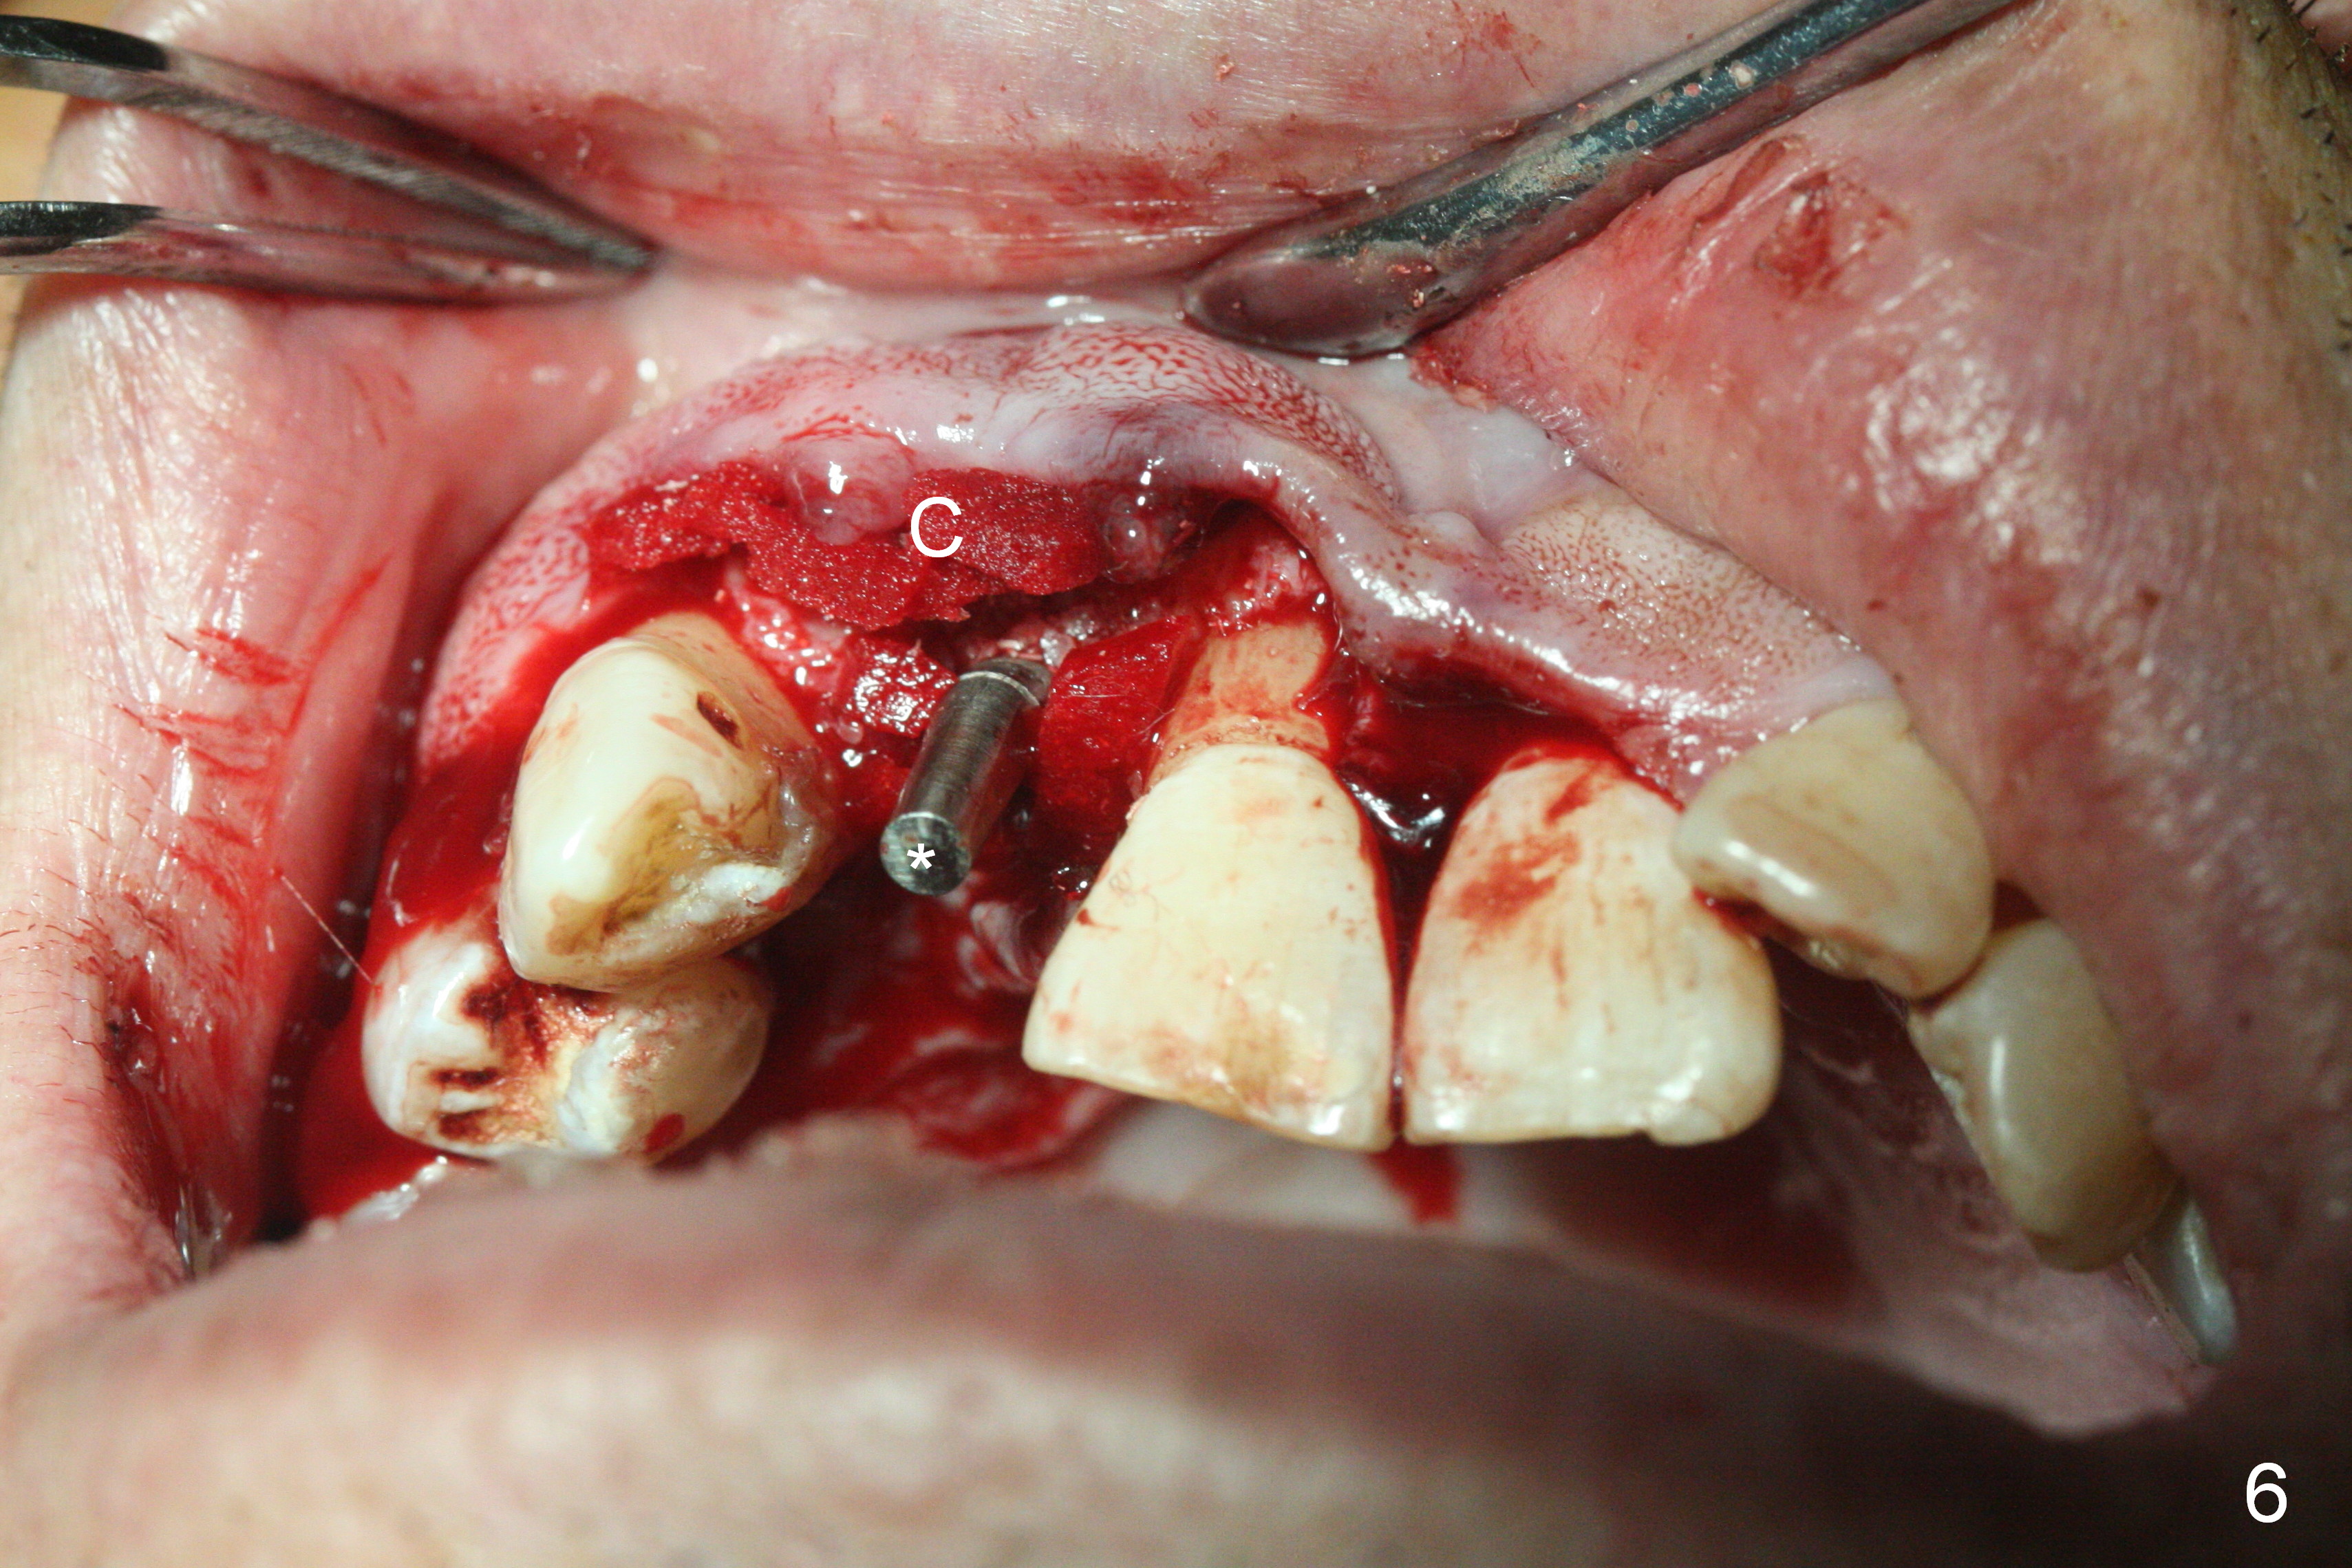

When the flaps are raised, the buccal plate is found to be perforated (Fig.2 *); osteotomy is being established in the narrow palatal wall (<). When a 3x17 mm (tissue-level) 15 ° 1-piece implant is placed (Fig.3,5 P), the incisal end of the implant is between the incisal edge of the central incisors and that of the tooth #10 (Fig.6) so that the temporary crown (Fig.7 T) is slightly buccal with sufficient palatal clearance with the opposing dentition.

Sixteen days postop, the patient is doing fine, although the labial fistula has not disappeared (Fig.8 <). The detached distolabial papilla is healing (Fig.9 *) with mild bone graft exposure (^). The lacerated distopalatal papilla is also healing (Fig.10 *). These complications are related to flap surgery. The apical portion of the socket appears to have reduced 4 months postop (Fig.14). When the definitive restoration is delivered 5 months postop, there is gingival recession, including the distal of #8 (Fig.11 arrows, which is expected to improve over time) due to flap surgery. The labial plate collapse is minimal (Fig.12 *), while the palatal laceration (Fig.10) has healed (Fig.13). When the patient returns 1.5 years post cementation, there is increased bone density next to the coronal portion of the implant, equivalent to the bone graft (Fig.15 *). The fistula is absent (Fig.16). The crestal bone loss remains 2.5 years post cementation (Fig.17 *), although there is no sign of periimplantitis (magnification). Oral hygiene is poor. There is no change in the soft (gingival recession; data not shown) or hard tissues 3 years 8 months post cementation (Fig.18).